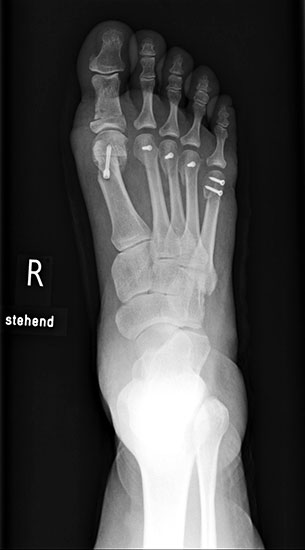

Die Fäden werden nach der 2. postoperativen Woche gezogen. Der Verbandsschuh wird für 4-6 Wochen getragen, anschließend erfolgt eine Röntgenkontrolle (Abb.16). Das Führen eines Kraftfahrzeuges mit diesem Schuh ist nicht gestattet. Eine Ausnahmekombination stellt die Operation des linken Fußes und Automatik-Fahrzeug dar.

Aus der klinischen Erfahrung heraus können die Patienten, bei unauffälligem Röntgenbild weiter mit einer entsprechenden Einlagenversorgung mit retrocapitaler Abstützung und ggf. notwendigen Modifikationen im weiten, bequemen Konfektionsschuh mobilisiert werden. Die klinischen Verlaufskontrollen in den letzten 14 Jahren haben gezeigt, dass bei korrekter Stellung zu diesem Zeitpunkt die osteotomierten Köpfchen auch in dieser Position verbleiben. Sollte eine korrekturbedürftige Fehlstellung vorliegen, ist diese 4 Wochen nach Primär-OP mit einem geringeren operativen Aufwand durchzuführen.